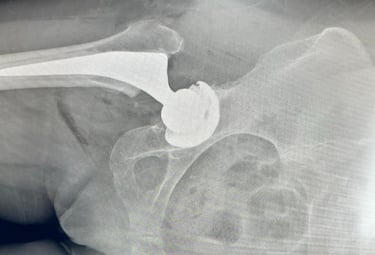

Reemplazo de Cadera

Encontrará los ejercicios para realizar la rehabilitación de su artroscopia de cadera. Esto es una guía para iniciar posteriormente a su cirugía

Galería Médica

Imágenes de procedimientos y técnicas en cirugía de cadera.